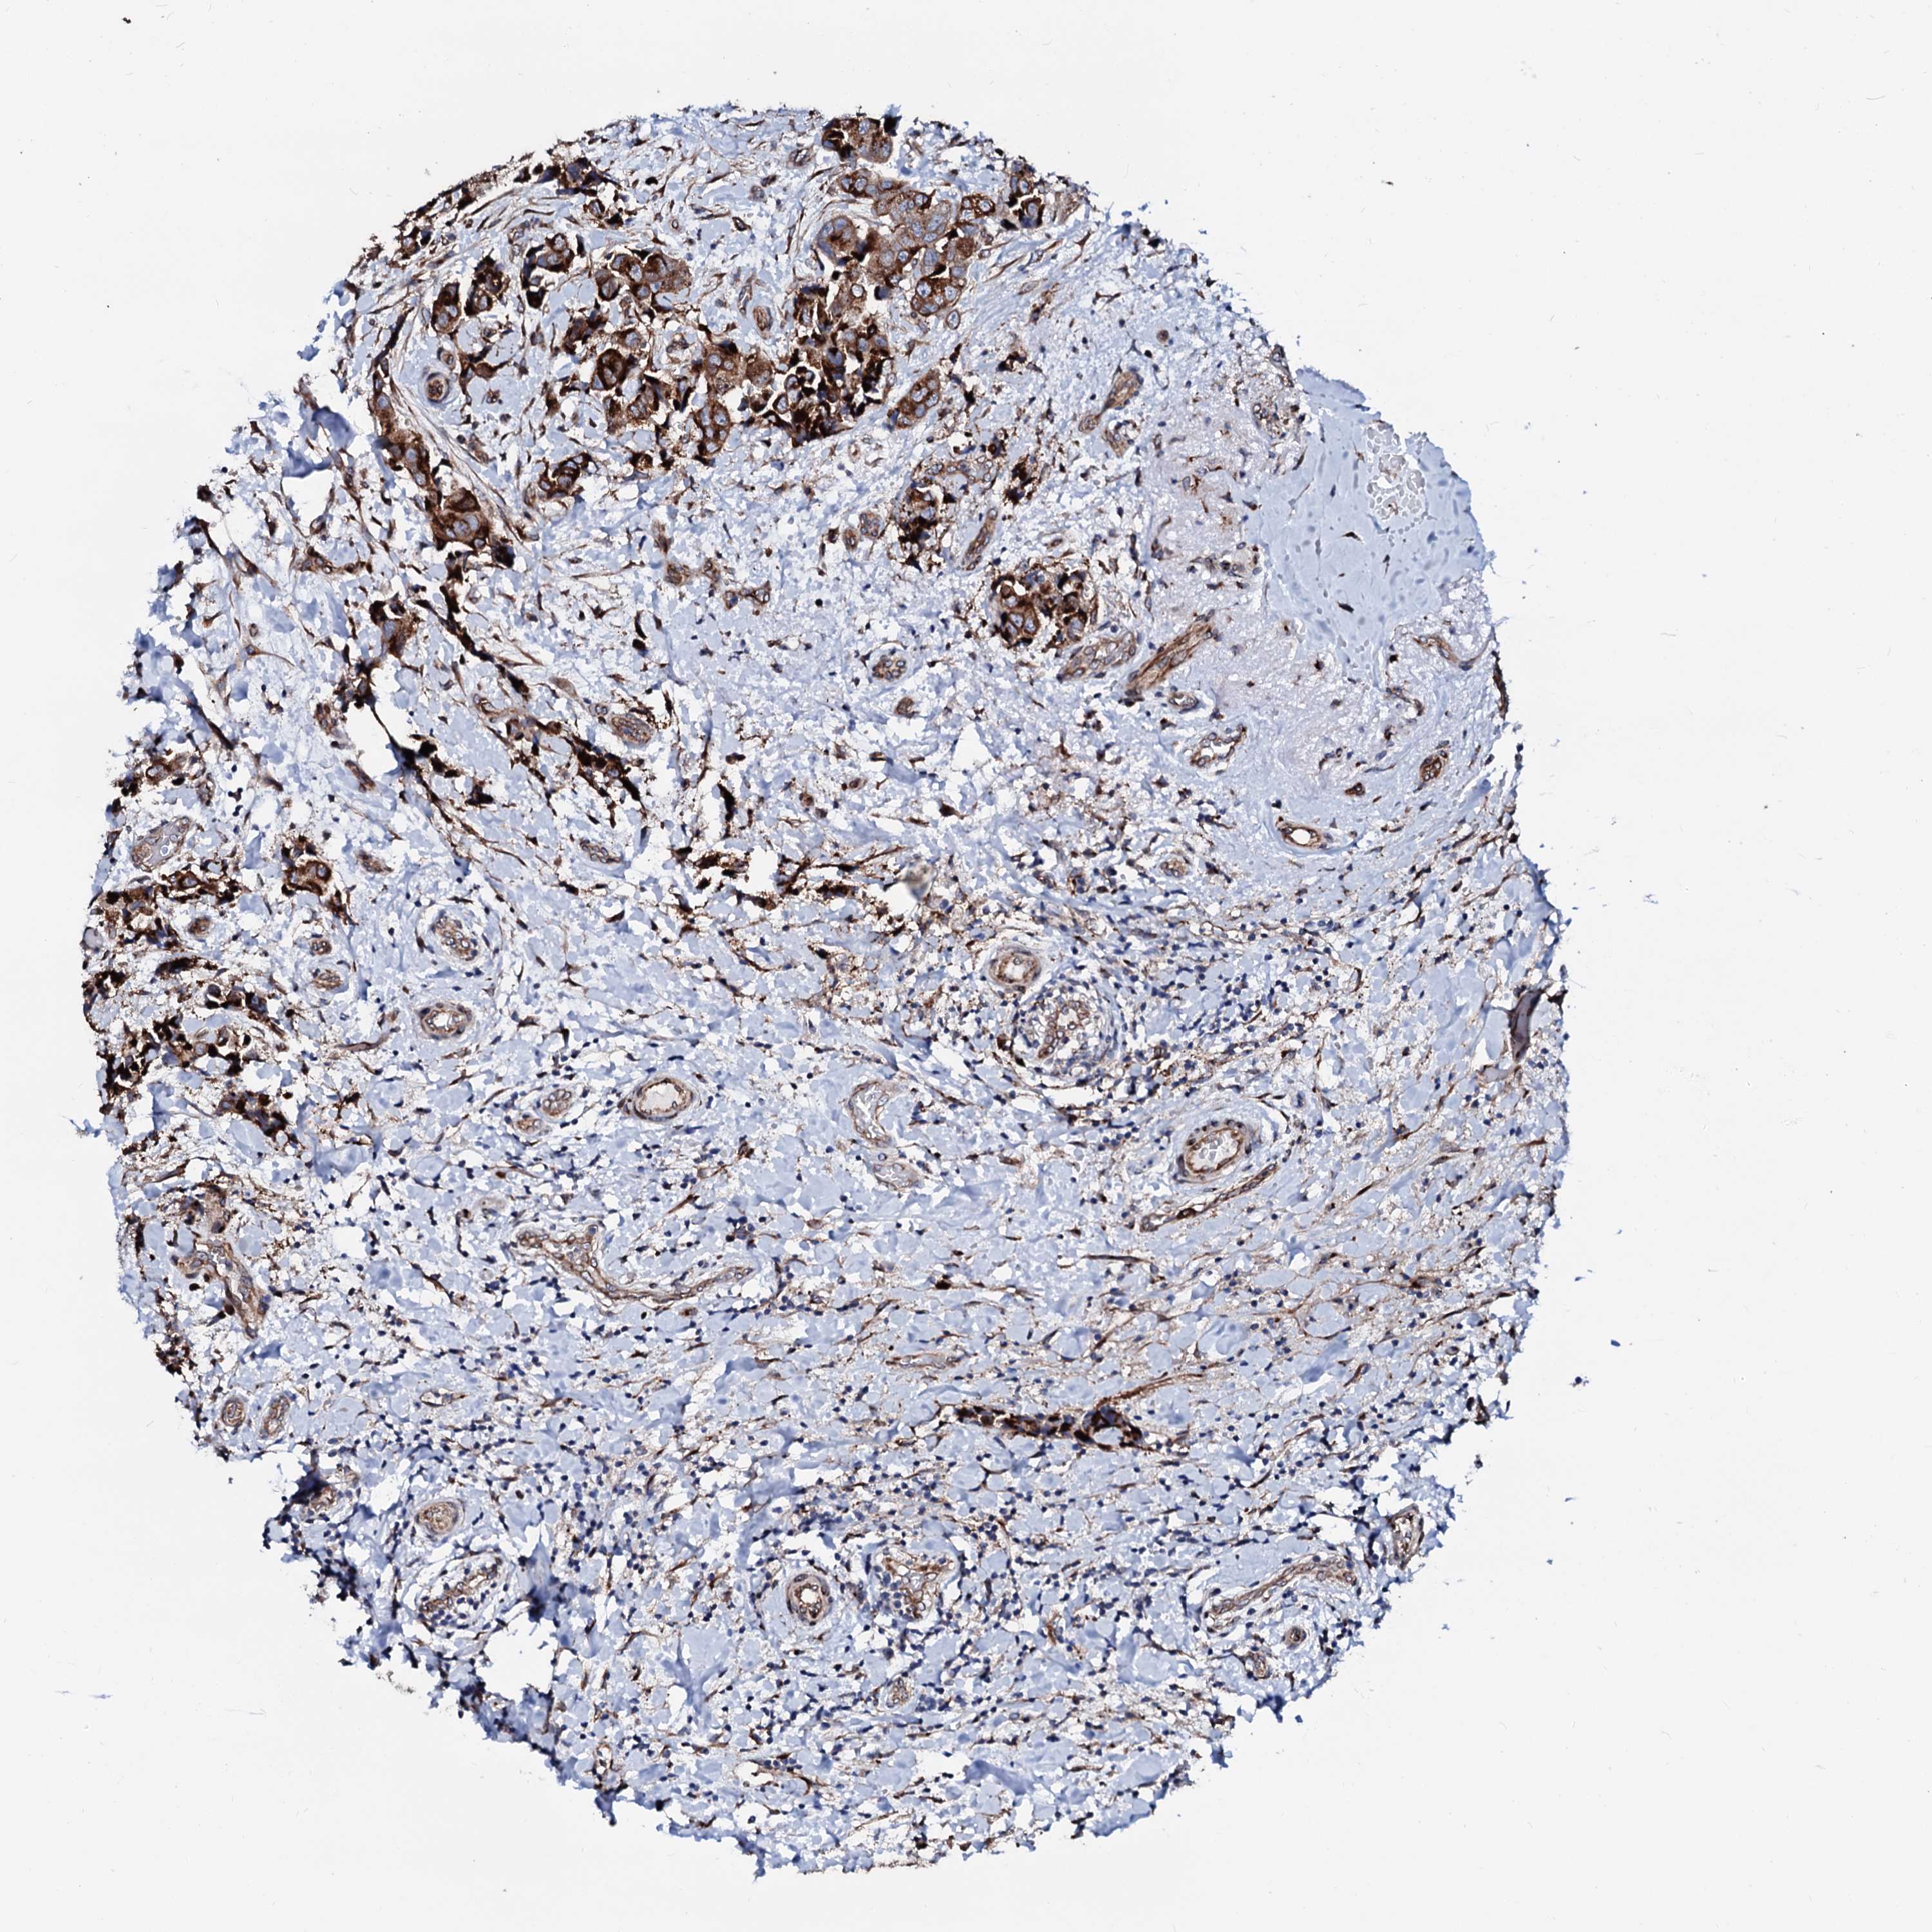

CANCER BREAST CANCER Show tissue menu

BRCA TCGA BRCA VALIDATION PROTEIN EXPRESSION

ANTIBODIES

AND

VALIDATION